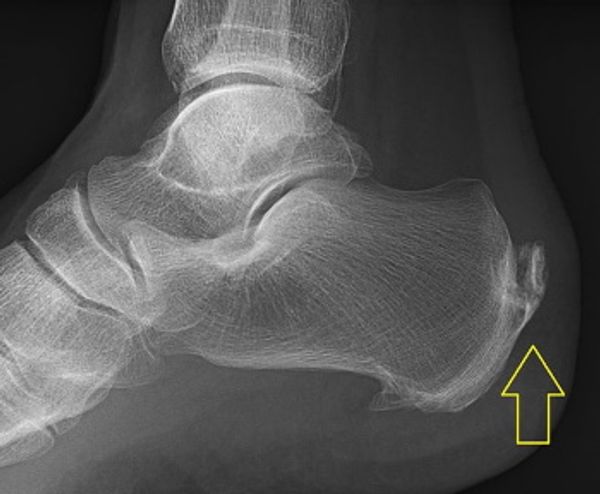

Leestijd: 5 minutenEs handelt sich um ein schmerzhaftes Leiden, an dem relativ viele Menschen zwischen 40 und 60 Jahren leiden. Fersensporn, dass sind Schmerzen unter dem Fersenbein beim Stehen und Gehen. Der Schmerz ist vergleichbar mit dem Schmerz, den man empfindet, wenn man einen Kieselstein im Schuh hat. Eigentlich ist die Bezeichnung Fersensporn nicht ganz richtig. Ein Fersensporn ist ein zusätzliches Knochenstück oder eine Verkalkung in der Nähe des Ansatzes der Fersensehne am Fersenbein (dem Calcaneum). Untersuchungen zeigen, dass 75 % aller Erwachsenen dieses zusätzliche Knochenstück, auch Fersenbein genannt, haben und dass dies nicht immer zu Beschwerden führt. Die Schmerzen werden wahrscheinlich durch den anhaltenden Druck dieses Knochens auf die Sehne in der Ferse verursacht, die sich dann entzünden kann. Wenn Sie Schmerzen an der Seite der Ferse verspüren, haben die Beschwerden nichts mit einem Fersensporn zu tun. Dann handelt es sich um andere Fußbeschwerden.

Foto: Lucien Monfils